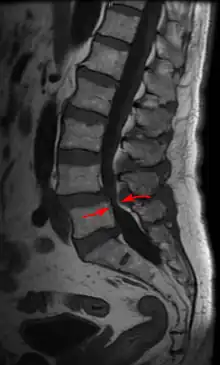

| Lumbar vertebra showing central stenosis and lateral recess stenosis. | |

Spinal stenosis may be congenital (rarely) or acquired (degenerative), overlapping changes normally seen in the aging spine.[6][7] Stenosis can occur as either central stenosis (the narrowing of the entire canal) or foraminal stenosis (the narrowing of the foramen through which the nerve root exits the spinal canal). Severe narrowing of the lateral portion of the canal is called lateral recess stenosis. The ligamentum flavum (yellow ligament), an important structural component intimately adjacent to the posterior portion of the dural sac (nerve sac) can become thickened and cause stenosis. The articular facets, also in the posterior portion of the bony spine can become thickened and enlarged, causing stenosis. These changes are often called "trophic changes" or "facet trophism" in radiology reports. As the canal becomes smaller, resembling a triangular shape, it is called a "trefoil" canal.